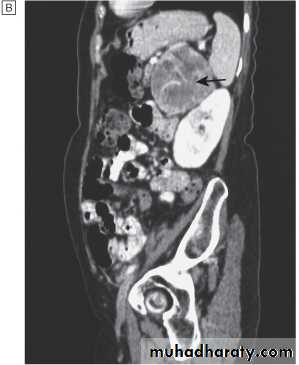

Localisation; abdominal CT or MRI.

CT scan of abdomen showing large left adrenal phaeochromocytoma. The normal right adrenal (white arrow) contrasts with the large heterogeneous phaeochromocytoma arising from the left adrenal gland (black arrows).